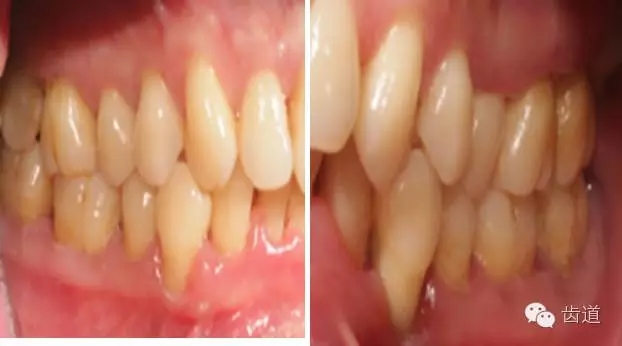

2、牙齦

(顏色、形狀、質(zhì)地、退縮、BOP、PD、附著齦)

6.webp.jpg

7.webp.jpg

8.webp.jpg

9.webp.jpg